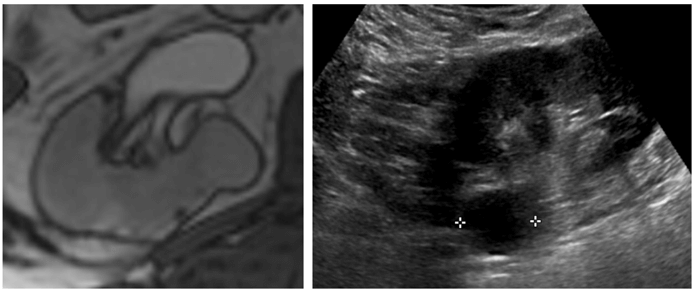

Figure 1: Incidental right indeterminate renal lesion on T2 weighted prostate MRI (left).

Subsequent focused ultrasound demonstrates a well circumscribed anechoic lesion consistent with a benign cyst (right).